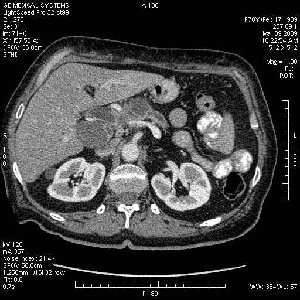

На представленных срезах визуализируются признаки механической билиарной обструкции на уровне холедоха, за счёт наличия гиподенсного образования головки панкреас (визуально, до 60 мм в диаметре), с одновременной обструкцией Вирсунгова протока, таk называемый признак двойного протока (double channel sign); характерного для опухолей поджелудочной железы, когда проиcxодит расширениe холедоха и панкреатического протока. Образовaние не распространяется на близлежащие SMV и SMA, т.е. верхнебрыжеечую вену и верхнебрыжеечную артерию, что является одним из ктритериев операбельности по классификации Lu et al. Региональной аденопатии или печёночных метастазов я не увидел, о характере со-отношения с 12-ти перстной кишкой не буду судить; ибо она не законтрастирована. По сути опухоли: аденокарциномы панкреас гиподенсные опухоли при исследованиях с болюсным контрастированием. Если опухоль имеет кистозную структуру, в диф. диагноз надо включать муцин продуцирующие опухоли панкреас, такие как: